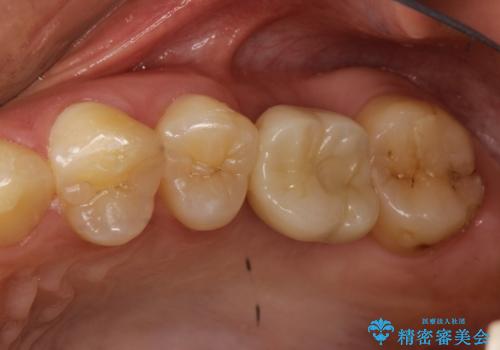

奥歯が割れてしまった! → インプラントによるかみ合わせの回復

歯がわれた 抜歯してインプラント 50代男性

左下奥歯 折れて抜歯 インプラントへ